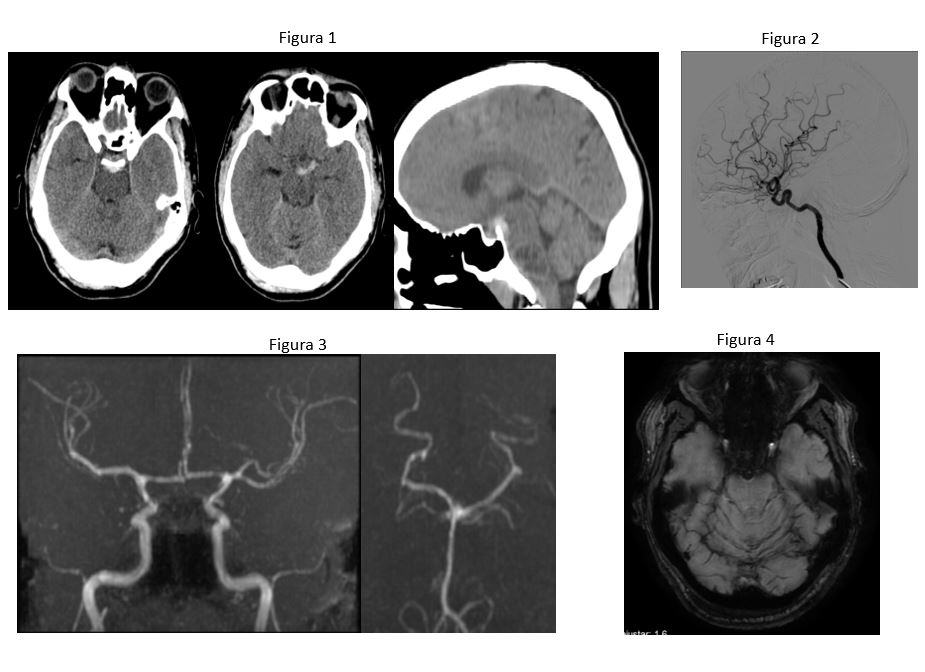

Figura 1. TC cabeza sin y tras contraste iv. Hemorrágia subaracnoidea aguda situada en cisternas perimesencefálicas con extensión al segmento proximal del valle silviano izquierdo.

Figura 2. Angiografía cerebral normal.

Figura 3. No se aprecia clara imagen de aneurisma circulación intracraneal en secuencia angiográfica 3DTOFF polígono sin gadolinio

Figura 4. En secuencia de susceptibilidad se detectan restos sideróticos en cisternas prepontomesencefálica. Leve siderosis superficial en las folias vermianas.